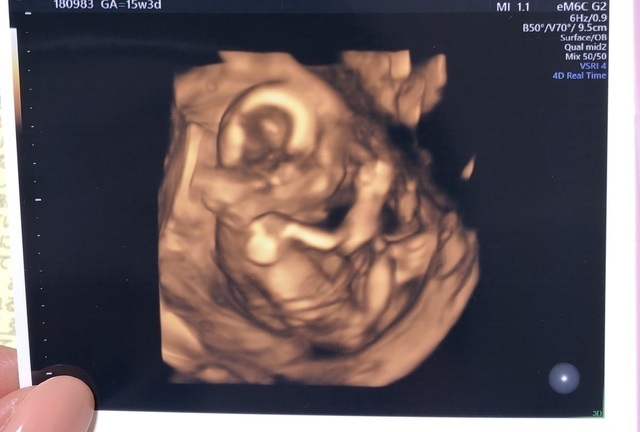

15週3日(15w3d・男の子)|kaaaa さん(25歳)

エコー写真撮影時のエピソード:

第二子にして初めて4Dエコーを貰った時のものです。まだ4ヶ月で胎動もなく今まで3Dエコーではぼんやりとした輪郭しか分からなかったのにちゃんと人の形になってる!!と感動しました。

主人も今まではエコーを見ても「ふーん」ぐらいの素っ気ない返事でしたが、これには喜んでくれました!やっぱり見やすい方が実感湧くのでしょうか。(笑)

上の子もまだ1歳でしたが、この頃から「ママのお腹には赤ちゃんがいるんだよ~~。こんなして寝んねしてるよ~~。」と話していました。毎日お腹をさすってくれて産まれる前からお姉ちゃんをしてくれています。